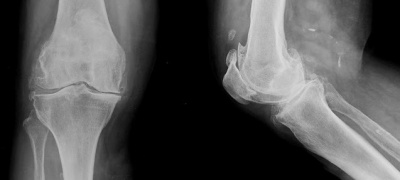

Oltre che sull'esame dei sintomi, la diagnosi della gonoartrosi si basa su un esame radiografico sotto carico il quale può confermare la diagnosi per la presenza dei segni radiografici tipici dell’artrosi cui corrispondono i relatici segni anatomo-patologici: diminuzione della rima articolare, osteofiti marginali, sclerosi dell’osso sub-condrale e cavità geodiche dell’osso sub-condrale.

In questi casi, in cui la gonoartrosi è in fase avanzata, sarebbero superfluo altri esami strumentali, i quali evidenziaranno l’usura e la degenerazione delle parti molli (cartilagine articolari e menischi).

Nelle fasi iniziali invece l’esame radiografico può risultare negativo poiché la patologia è ancora limitata all’ambito cartilagineo. In questi casi è consigliato quindi un esame strumentale più approfondito come la Risonanza Magnetica.